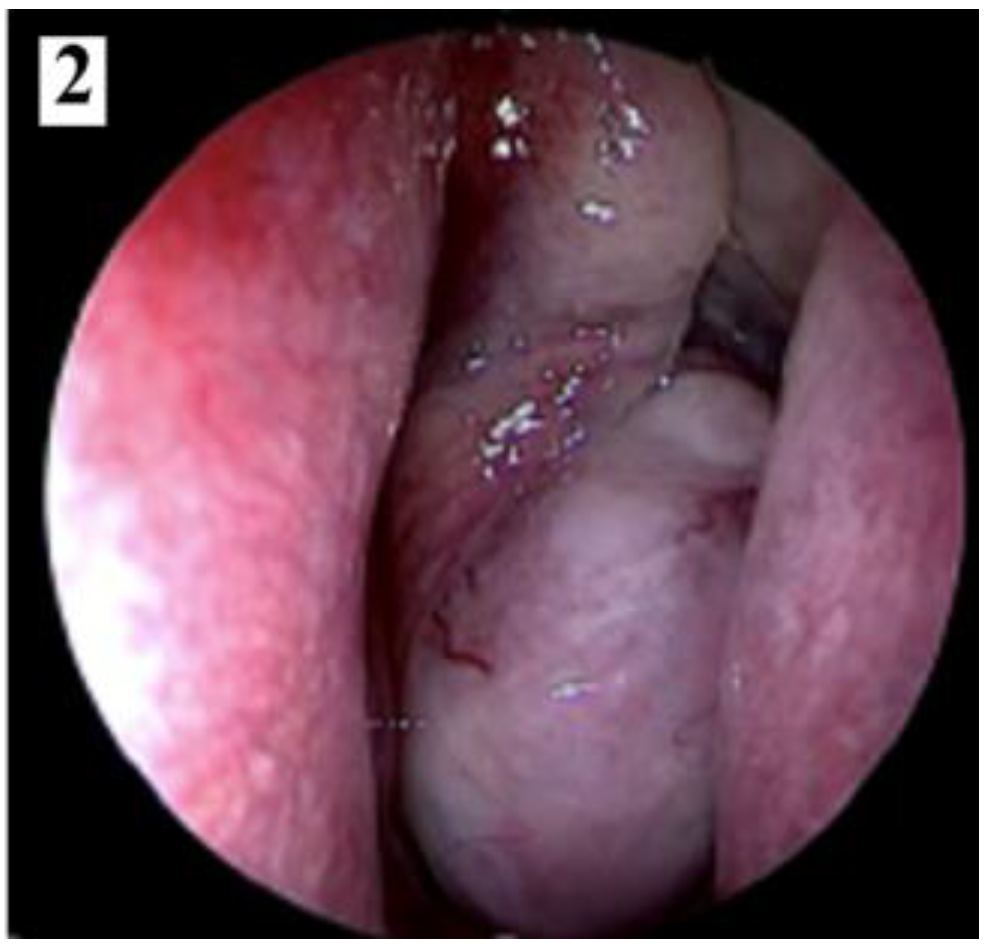

Nasal endoscopy shows a smooth, lobulated mass, pale or grey-red, intensely congestive, compressible, usually originating from behind the tail of the middle turbinate, that may occupy the entire nasal fossa and determine the obstruction of the choana.

Figure 1. Smooth, lobulated, pale or grey-red, intensely congestive, compressible mass (part 1).

Figure 2. Smooth, lobulated, pale or grey-red, intensely congestive, compressible mass (part 2).